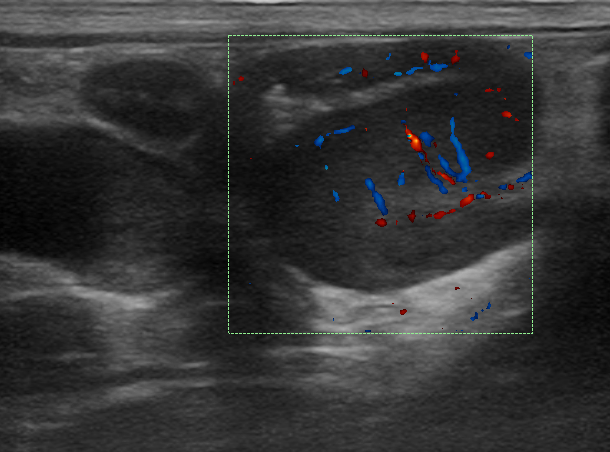

EVOLUÇÃO: INDICAÇÃO DE EXAME ULTRASSONOGRÁFICO

- Foi realizado exame ultrassonográfico abdominal que revelou presença de discreta quantidade de líquido livre em cavidade abdominal, linfonodos esplênico e mesentéricos acentuadamente aumentados e de ecotextura heterogênea. Visibilizou-se uma estrutura parenquimatosa aderida a um segmento de alça intestinal jejunal, homogênea, de formato ovalado, medindo 2,14cm x 1,44cm, vascularizada ao Doppler colorido e que invadia e obstruía parcialmente o lúmen intestinal, sugerindo processo neoplásico.

Doppler estrutura 1º exame